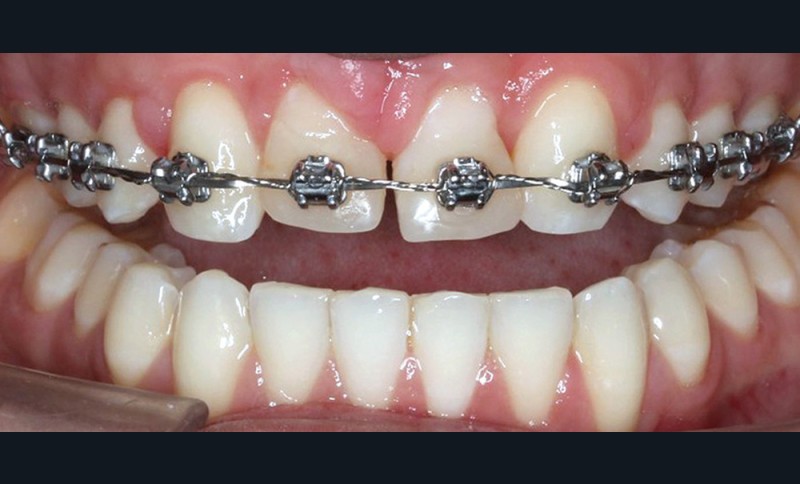

Dans un premier temps, l’extraction des 11 et 21 est réalisée. Un bouton est collé sur la 13, visible dans l’alvéole de la 11 afin de permettre sa désinclusion (fig. 2). La traction se fait à l’aide d’un arc TMA .016 x .022 en overlay afin d’avoir un axe de traction horizontal et vestibulaire évitant une résorption de la 12 à cette étape (fig. 3a,b) [3]. Ne pouvant pas mettre d’arc de Nance du fait de la position palatine des incisives latérales, il est convenu que des minivis d’ancrage peuvent être nécessaires si une perte d’ancrage postérieure est constatée (ce qui n’est pas le cas).

Une fois la 13 à l’aplomb de son alvéole, une traction verticale de cette dent peut être réalisée. La 12 n’est pas prise en charge avant la correction de la transposition afin de limiter le risque de résorption de cette dent. La difficulté est alors la gestion des torques antérieurs perturbés, liés aux déplacements réalisés.

Après avoir ménagé des espaces suffisants pour maquiller 12 et 22 en 11 et 21, des restaurations composites sont réalisées au sein du cabinet d’orthodontie sans tenir compte précisément des axes radiculaires, afin de rétablir le plus rapidement possible une esthétique acceptable.